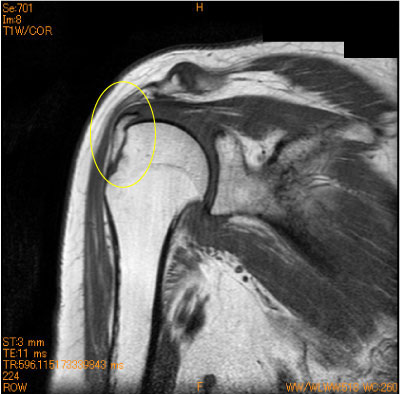

60代女性、登山で滑落。

大結節の剥離骨折は知られていないが、形態と骨挫傷が少ないことから剥離骨折が疑われる。

![]() Obl. Cor T1WI |